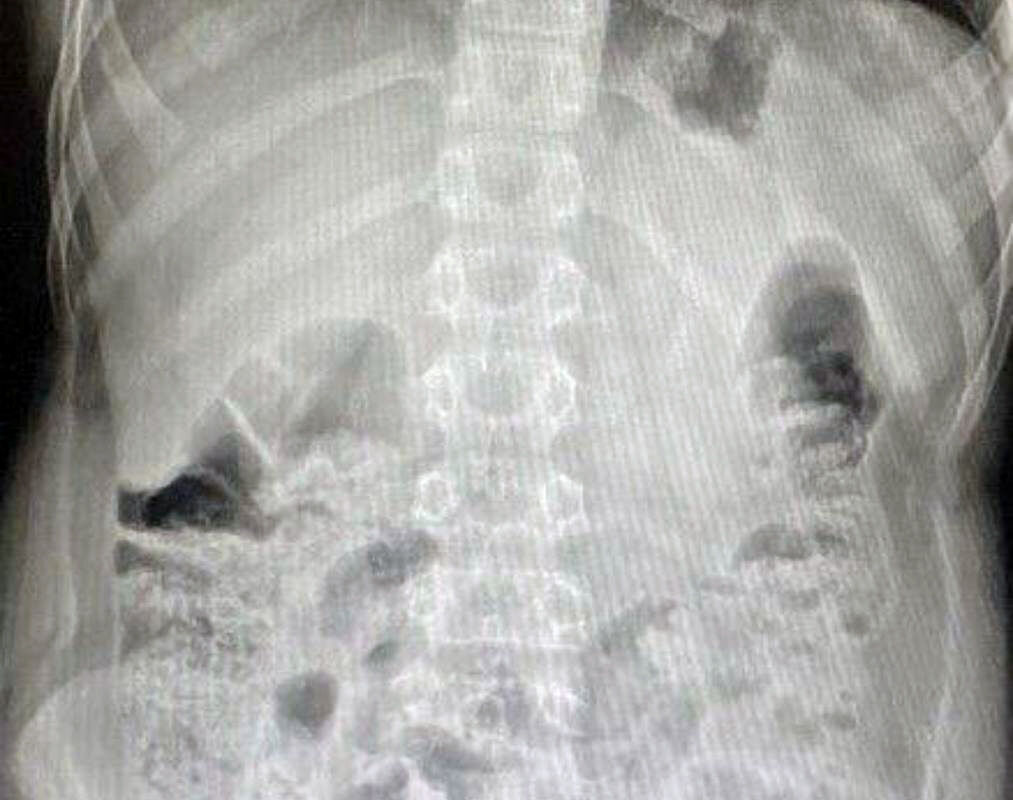

В медучреждение 12-летнего пациента привезли родители. Они рассказали, что сын проглотил батарейку из пульта от телевизора. Между моментом инцидента и обращением за помощью прошло очень мало времени. За это время инородное тело успело опуститься в слепую кишку. Врачи приняли решение о немедленном извлечении предмета.

«Вначале выполнили лапароскопию, чтобы визуализировать как возможные осложнения, так и расположение инородного предмета. Затем провели эндоскопическое исследование, во время которого с помощью специальной петли извлекли литиевую батарейку», — поделился детский хирург, заведующий хирургическим отделением №1 Игорь Хворостов.